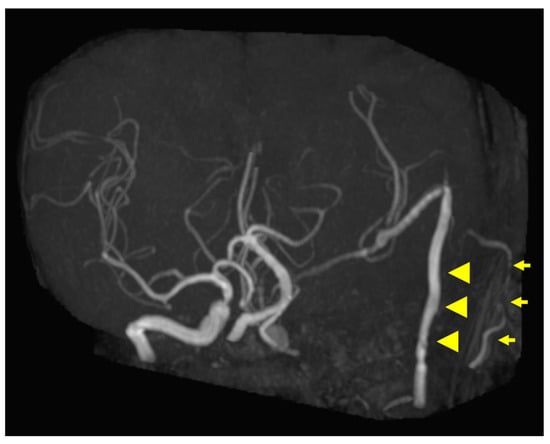

Figure 5. Postoperative magnetic resonance angiography (MRA) findings. MRA shows high-flow radial artery bypass between the M2 segment of the left middle cerebral artery (MCA) and the left cervical external carotid artery, with an additional superficial temporal artery (STA)–MCA bypass. Peripheral cerebral blood flow is maintained by the bypasses. The left internal carotid artery is trapped, and no blood flow is observed. Arrowheads indicate the high-flow bypass, and arrows indicate the STA–MCA bypass.